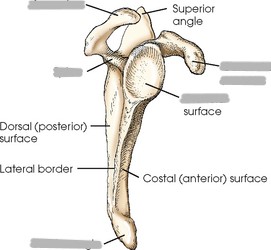

What is the anterior surface of the scapula called?

costal surface (comes in contact with the ribs)

What is the posterior surface of the scapula called?

dorsal surface